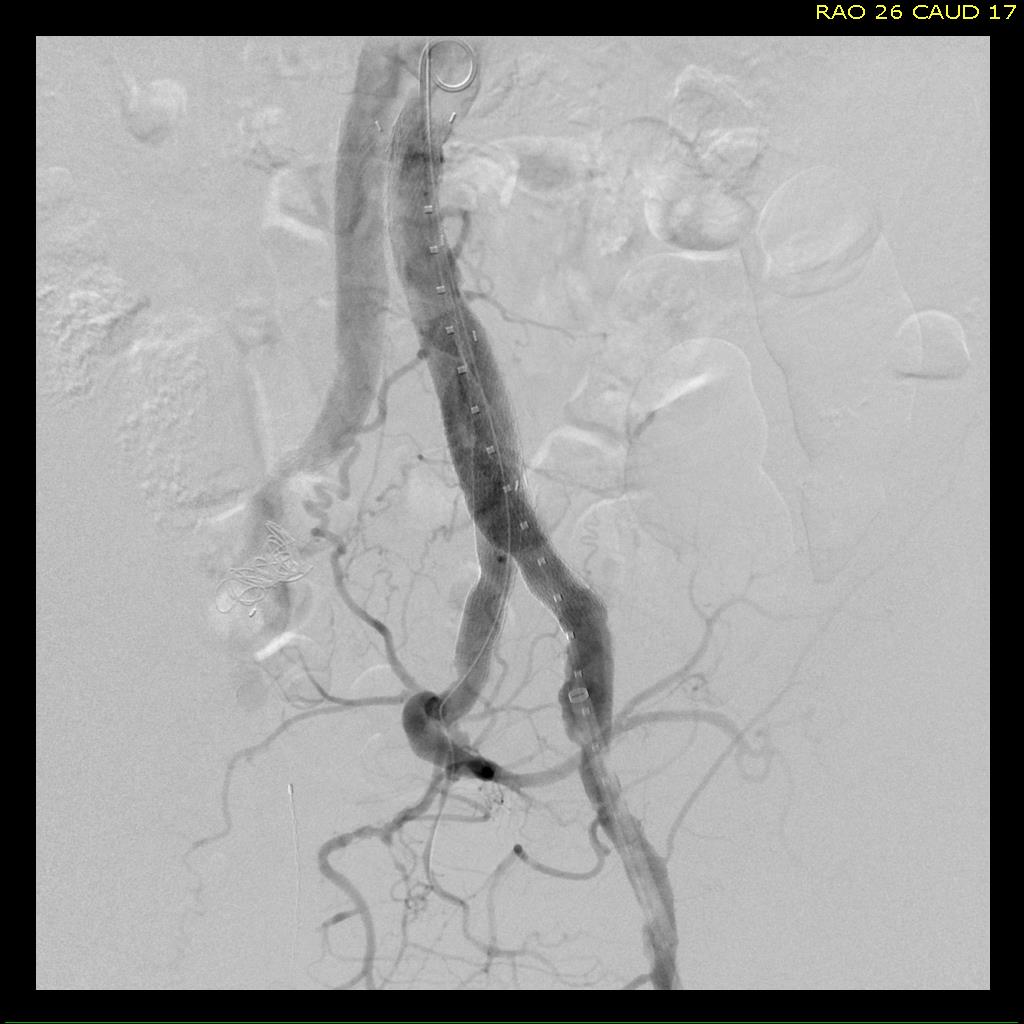

For example, take this patient who after EVAR of aortic aneurysm with AFX developed metachronous dilatation of the common iliac artery to 3.9cm with abdominal pain. The average diameter is 18.5mm. From the table, that rounds to 19mm corresponding to 283.53 square mm. If the internal iliac artery requires a 13mm graft, that is 132.73 square mm, the difference being 150.80 square mm. That corresponds to a 14mm diameter graft, but a slightly larger graft is preferred for oversizing. The external iliac artery is 8mm, and putting a 13mm Viabahn (largest available) in that would result in the B-infolding in the 8mm external iliac. Here, I bailed myself out by simply placing a 20mm AFX iliac limb extension, which by virtue of its design is resistent to infolding and tolerant of parallel grafts laid alongside in constricted channels. I found that the AFX iliac limb, a 20-13mm x 88mm length extension well suited for this.

The AFX graft limb seems to adapt to the presence of the parallel “sandwich” graft which is deployed second and ballooned last. In followup, there was shrinkage of the common iliac artery aneurysm sac and no endoleak.

Compared to my other parallel graft case treating a metachronous saccular common iliac aneurysm years after an EVAR with a Gore endograft (link), which by table calculation, resulted in 8% oversize in calculated areas, this particular technique with a large AFX graft and an appropriately sized Viabahn seemed to work well the setting of a previously placed AFX graft. It allows one to avoid hypogastric occlusion.